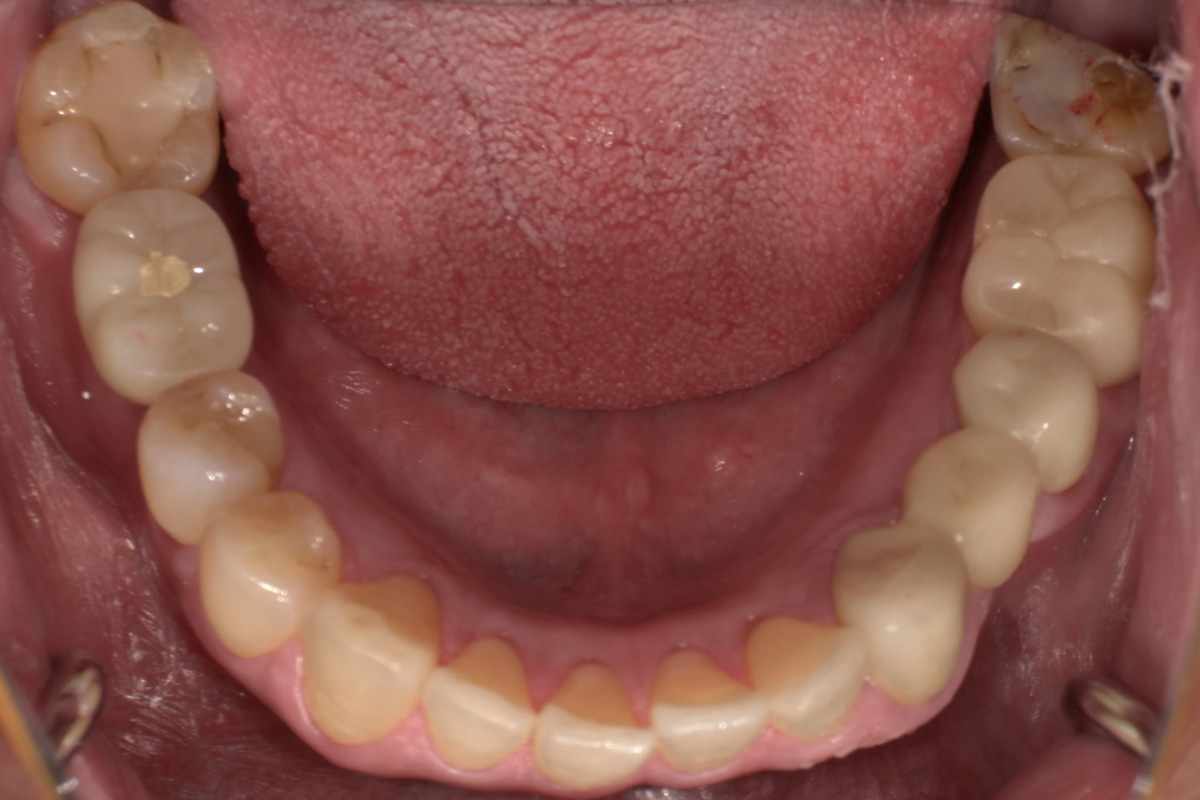

初診時

歯が割れていて、痛みがあり、抜歯となりました。

パノラマレントゲン写真 -